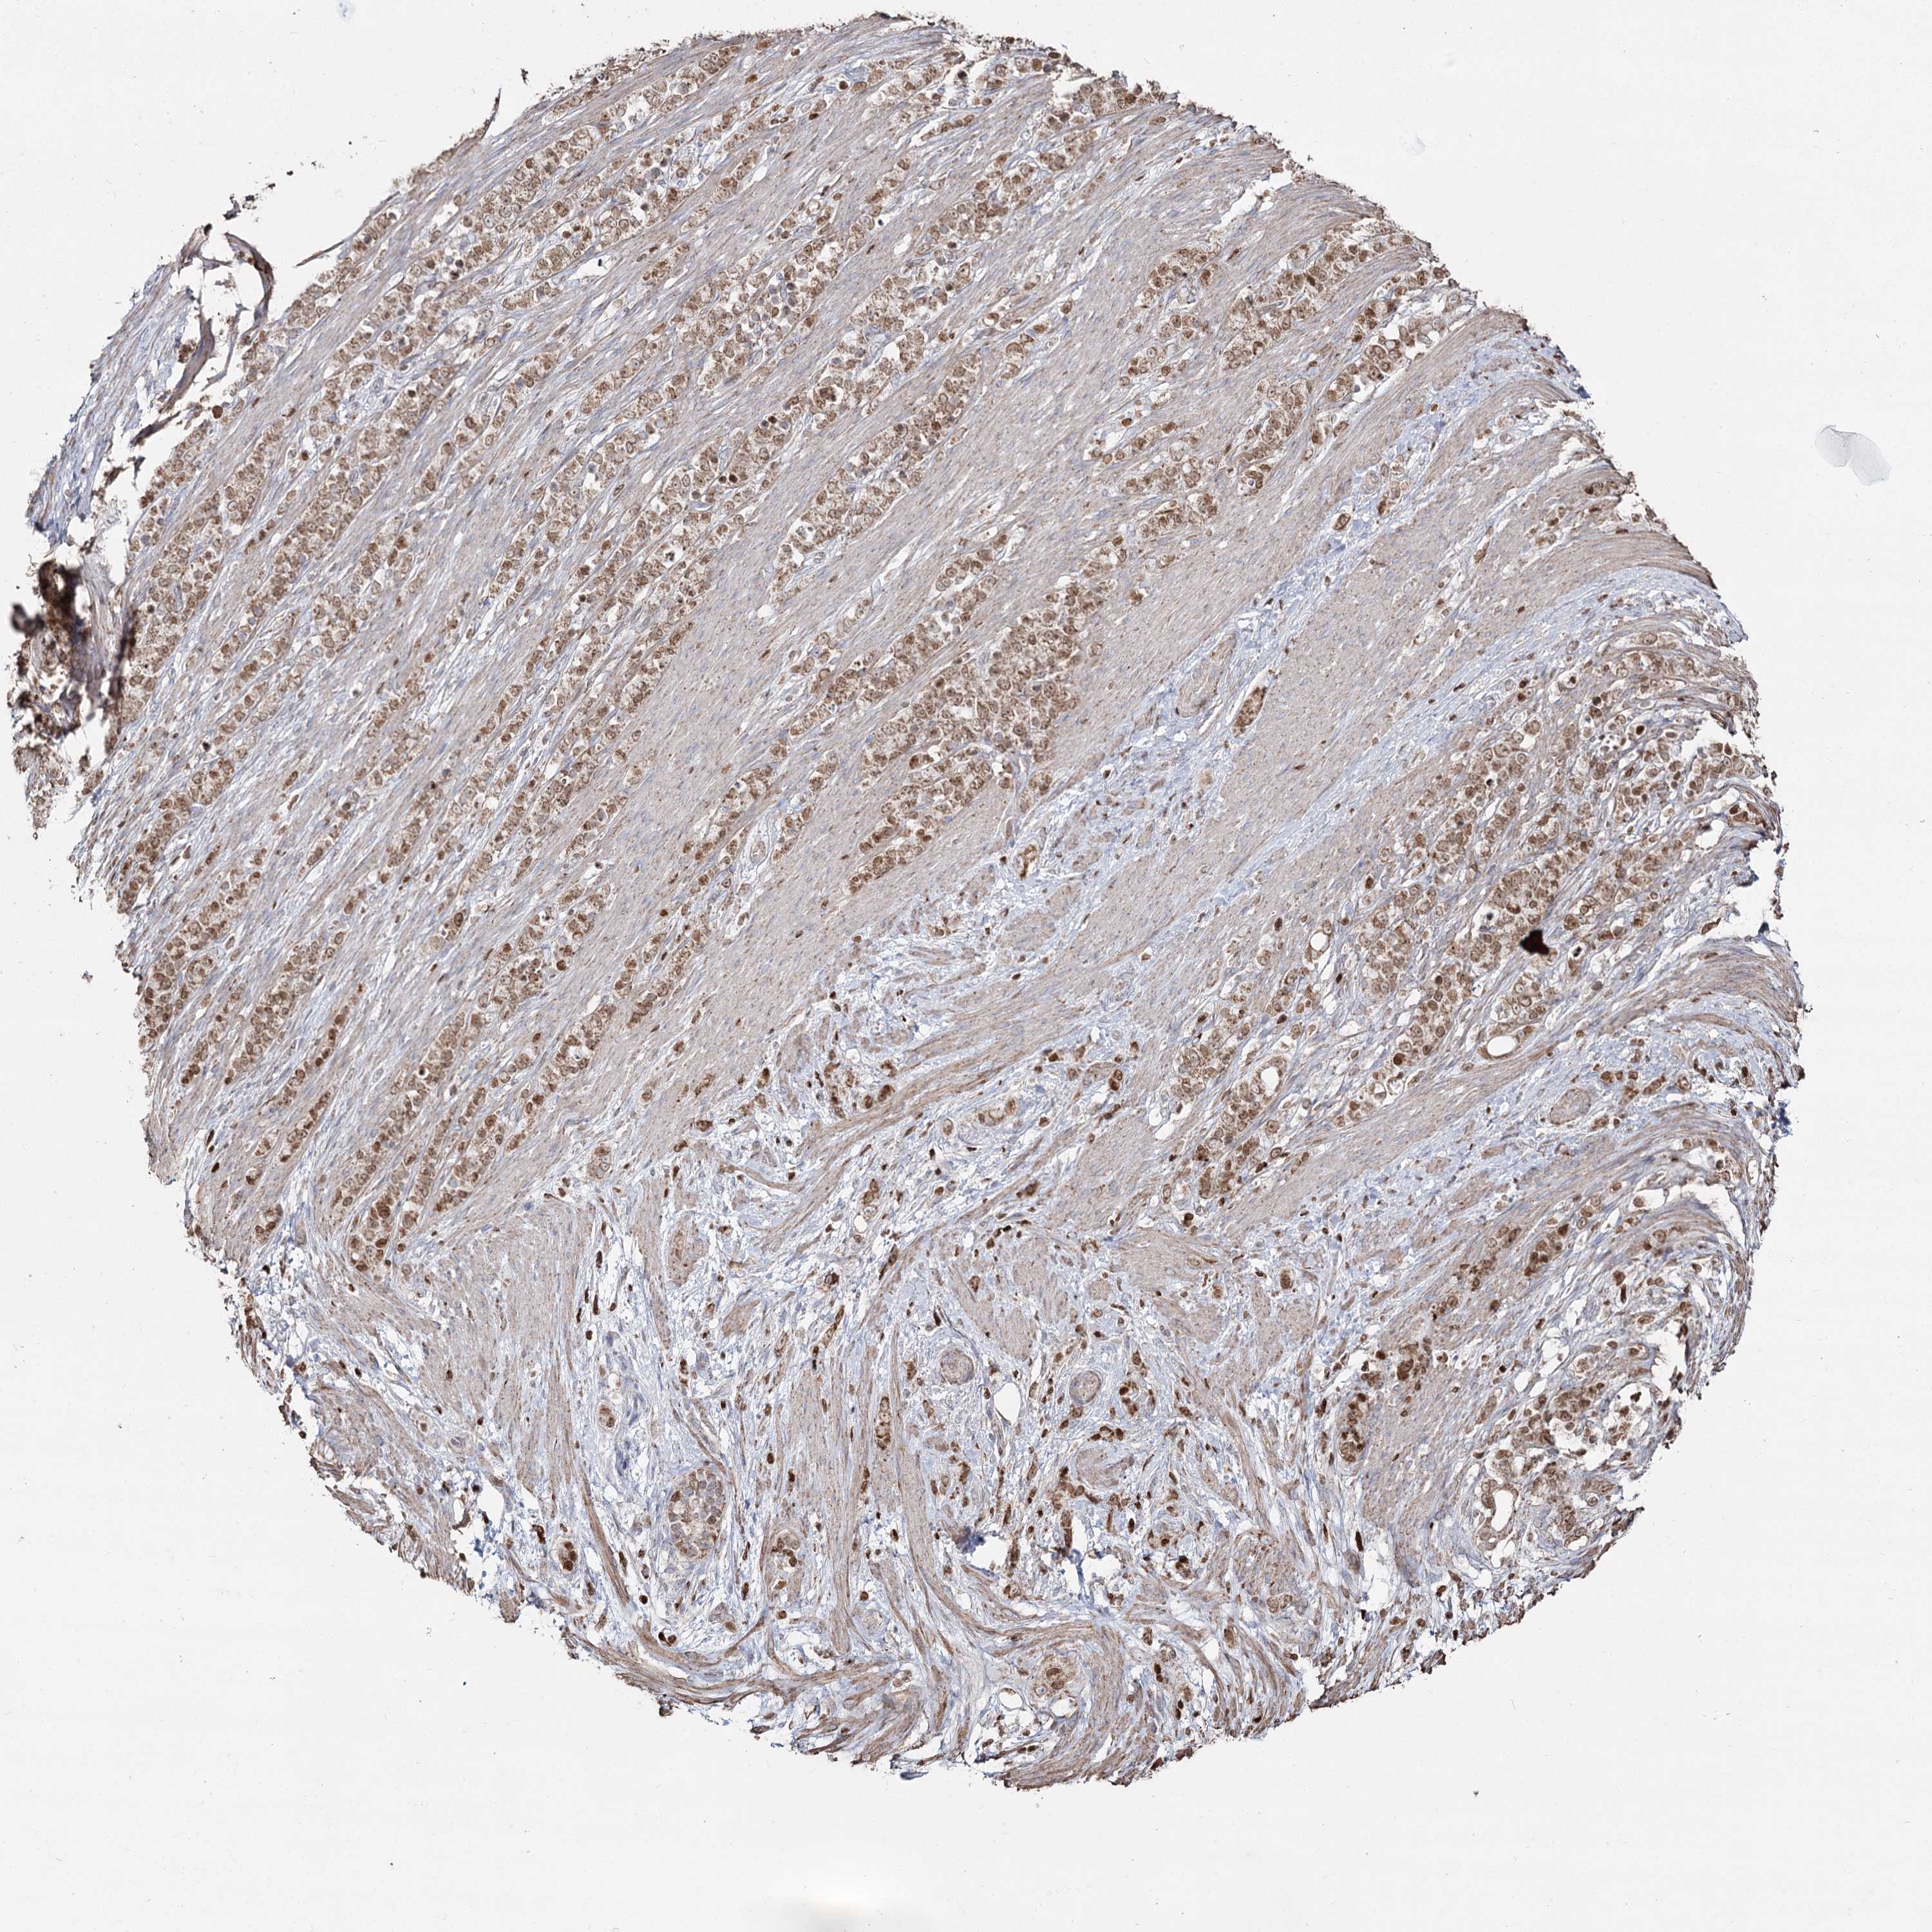

STOMACH CANCER - Protein expressioni

A mouse-over function shows sample information and annotation data. Click on an image to view it in a full screen mode. Samples can be filtered based on level of antibody staining by selecting one or several of the following categories: high, medium, low and not detected. The assay and annotation is described here.

Note that samples used for immunohistochemistry by the Human Protein Atlas do not correspond to samples in the TCGA dataset.

Antibody stainingi

Antibody staining in the annotated cell types in the current human tissue is reported as not detected, low, medium, or high, based on conventional immunohistochemistry profiling in selected tissues. This score is based on the combination of the staining intensity and fraction of stained cells.

Each image is clickable and will lead to virtual microscopy that enables deeper exploration of all samples and also displays staining intensity scores, fraction scores and subcellular localization as well as patient and tissue information for each sample.

Antibody HPA038484

Antibody HPA038485

Staining

High

Medium

Low

Not detected

Intensity

Strong

Moderate

Weak

Negative

Quantity

>75%

75%-25%

<25%

None

Location

Nuclear

Cytoplasmic/membranous

Cytoplasmic/membranous,nuclear

Adenocarcinoma, NOS

Adenocarcinoma, High grade